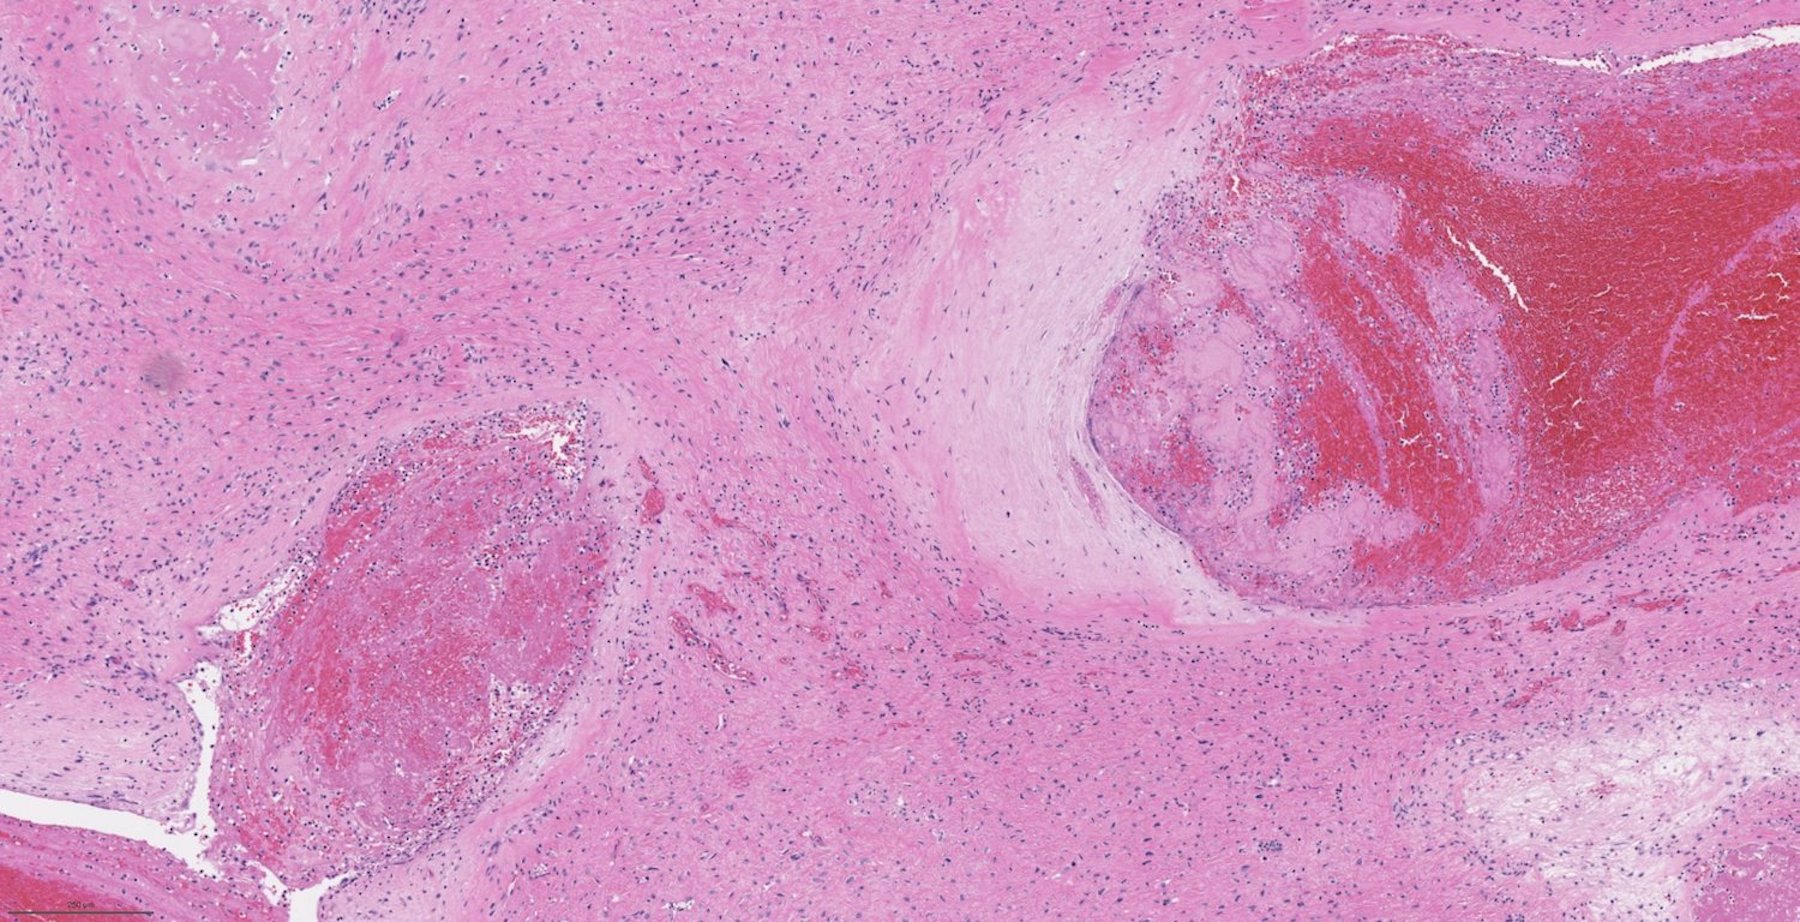

Microscopic (histologic) description

- Benign fibrovascular lesion composed of 2 components

- Vascular space of various sizes, ranging from dilated branching vessel of various thickness to slit-like capillaries

- Fibrous or collagenous stroma with fibroblasts

- Central area of the tumor is typically cellular, composed of fibroblasts or myofibroblasts with spindle, round or stellate morphology

- Stroma can be fibrous, edematous or collagenized

- Fibrinous thrombi may be seen in dilated vessels

Microscopic (histologic) images

Contributed by Bin Xu, M.D., Ph.D.

Contributed by Kelly Magliocca, D.D.S., M.P.H.